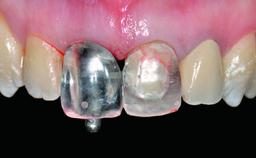

A 32-year-old female Caucasian patient with a compromised maxillary right central incisor was referred to us by a general dentist. Her chief complaints were discomfort and mobility of tooth 11 with unsatisfactory esthetics due to discoloration. The patient reported a previous trauma, some years earlier, as the origin of pathology on the afflicted tooth. Anamnesis was negative for any other dental or periodontal pathology in the remaining dentition. The patient did not take any medication and reported to be a light smoker (5–10 cigs/day). She had high esthetic expectations of her treatment. The extraoral examination revealed a high smile line with full exposure of her maxillary teeth and surrounding soft tissue in the area between the second premolars.

Defining Characteristics One missing tooth to be replaced by an implant-borne crown

Loading Protocol Conventional or early

Retention Screw-retained Screw-retained

Provisional Implant-Supported Prosthesis Prosthodontic margin > 3 mm apical to mucosal margin Prosthodontic margin > 3 mm apical to mucosal margin

Interim Prosthesis during Healing Fixed Fixed